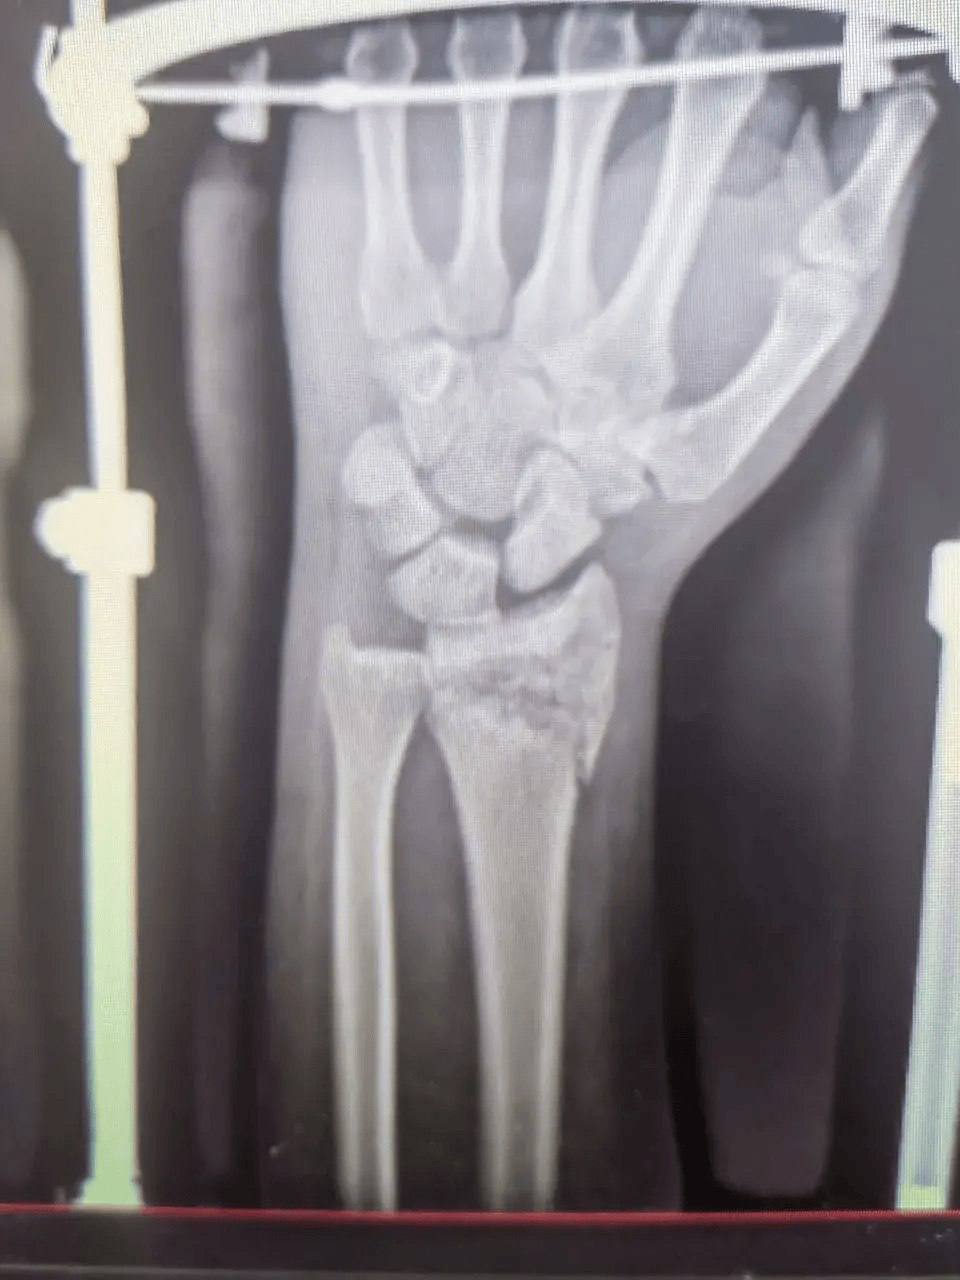

В больницу скорой помощи поступил 52-летний мужчина с тяжёлой политравмой после падения. У него были множественные переломы и повреждения, требующие комплексного лечения.

К работе подключилась команда специалистов: челюстно-лицевые хирурги, травматологи, нейрохирурги и неврологи провели операции и терапию. Несмотря на осложнение в виде токсического гепатита, врачам удалось стабилизировать состояние пациента.